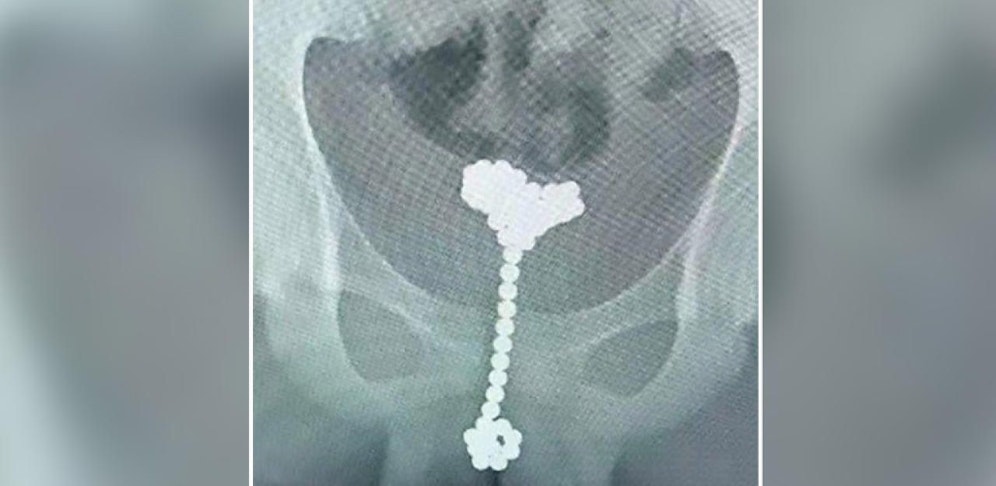

Einem 12-jährigen Chinesen mussten insgesamt 31 Magnetkugeln aus seinem Penis und seiner Blase geholt werden. Der Bub hatte sich die Kugeln selbst eingeführt.

Die Aufnahmen, die im Wuhan Children's Hospital in China gemacht wurden und derzeit im Internet die Runde machen, sind nichts für schwache Nerven.

Der Bub hatte die Kugeln zu einer langen Kette geformt und anschließend in seine Harnröhre geschoben. Die Ärzte pumpten daraufhin Luft in die Blase und zogen die Kugeln wieder heraus.